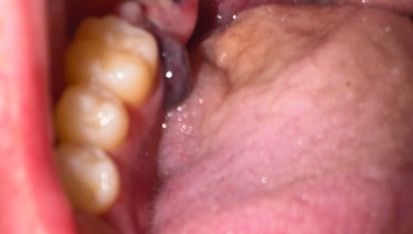

사랑니 발치 후 혈병과 잇몸이 이상해서 그런데 괜찮은건가요?

사랑니 발치 후 혈병이 옆에 잇몸에 달라붙는것과 잇몸이 부은 현상이 있는데 괜찮은걸까요??

눌렀을 때는 말랑말랑한 느끼이며 통증은 없습니다..

혈병은 발치와 안에서부터 차오르는데요. 저건 겉에 있는 피 덩어리 정도로 생각하시면 되겠습니다. 발치후에는 당연히 붓고 아프기 때문에 아직 걱정하진 않으셔도 되겠습니다.

사진을 봤을 경우에는 사랑니를 발치한 부위가 손상이 많이 되어 있는것으로 보입니다. 이런 손상된 부위는 시간이 지나면서 아물기 때문에 해당부위를 자극하지 않는것이 좋습니다.